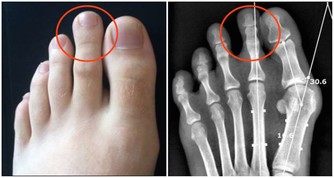

腦下垂體生長動情激素、內分泌失調、心理神經敏感、易怒、不自信、多疑,頸椎變形,

會造成腰椎變形,腰椎變形會壓迫坐骨神經,坐骨神經會壓迫附盆腔,

同時引發內分泌失調:腰酸背痛,腿腳無力,易疲勞,內分泌失調,月經不調,痛經,易肥胖,婦科感染,性生活失調,宮頸糜爛,子宮肌瘤等等。